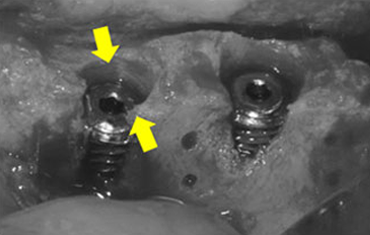

임플란트 식립과 동시에 뼈이식을 하는 경우

폭이 많이 부족하여 뼈이식을 먼저 한 후, 임플란트 식립을 하는 경우